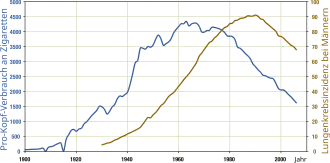

German scientists identified a link between smoking and lung cancer in the late 1920s, leading to the first anti-smoking campaign in modern history, albeit one truncated by the collapse of Nazi Germany at the end of World War II.[10] In 1950, British researchers demonstrated a clear relationship between smoking and cancer.[11] Evidence continued to mount in the 1960s, which prompted political action against the practice. Rates of consumption since 1965 in the developed world have either peaked or declined.[12] However, they continue to climb in the developing world.[13] As of 2008 to 2010, tobacco is used by about 49% of men and 11% of women aged 15 or older in fourteen low-income and middle-income countries (Bangladesh, Brazil, China, Egypt, India, Mexico, Philippines, Russia, Thailand, Turkey, Ukraine, Uruguay, and Vietnam), with about 80% of this usage in the form of smoking.[14] The gender gap tends to be less pronounced in lower age groups.[15][16] According to the World Health Organization, 8 million annual deaths are caused by tobacco smoking.[17]

In 1912 and 1932 in Germany, anti-smoking groups, often associated with anti-liquor groups,[36] first published advocacy against the consumption of tobacco in the journal Der Tabakgegner (The Tobacco Opponent). In 1929, Fritz Lickint of Dresden, Germany, published a paper containing formal statistical evidence of a lung cancer–tobacco link. During the Great Depression, Adolf Hitler condemned his earlier smoking habit as a waste of money,[37] and later with stronger assertions. This movement was further strengthened with Nazi reproductive policy as women who smoked were viewed as unsuitable to be wives and mothers in a German family.[38] In the 20th century, smoking was common. Social events like the smoke night promoted the habit.

The anti-tobacco movement in Nazi Germany did not reach across enemy lines during the Second World War, as anti-smoking groups quickly lost popular support. By the end of the Second World War, American cigarette manufacturers quickly reentered the German black market. Illegal smuggling of tobacco became prevalent,[39] and leaders of the Nazi anti-smoking campaign were silenced.[40] As part of the Marshall Plan, the United States shipped free tobacco to Germany; with 24,000 tons in 1948 and 69,000 tons in 1949.[39] Per capita yearly cigarette consumption in post-war Germany steadily rose from 460 in 1950 to 1,523 in 1963.[10] By the end of the 20th century, anti-smoking campaigns in Germany were unable to exceed the effectiveness of the Nazi-era climax in the years 1939–41 and German tobacco health research was described by Robert N. Proctor as "muted".[10]

In 1950, Richard Doll published research in the British Medical Journal showing a close link between smoking and lung cancer.[41] Beginning in December 1952, the magazine Reader's Digest published "Cancer by the Carton", a series of articles that linked smoking with lung cancer.[42]

In 1954, the British Doctors Study, a prospective study of some 40 thousand doctors for about 2.5 years, confirmed the suggestion, based on which the government issued advice that smoking and lung cancer rates were related.[11] In January 1964, the United States Surgeon General's Report on Smoking and Health likewise began suggesting the relationship between smoking and cancer.[43]

From 1965 to 2006, rates of smoking in the United States declined from 42% to 20.8%.[12] The majority of those who quit were professional, affluent men. Although the per-capita number of smokers decreased, the average number of cigarettes consumed per person per day increased from 22 in 1954 to 30 in 1978. This paradoxical event suggests that those who quit smoking smoked less, while those who continued to smoke moved to smoke more light cigarettes.[45] The trend has been paralleled by many industrialized nations as rates have either leveled-off or declined. In the developing world, however, tobacco consumption continued to rise at 3.4% in 2002.[13] In Africa, smoking is in most areas considered to be modern, and many of the strong adverse opinions that prevail in the West receive much less attention.[46] In 2008, Russia (70.2%), Indonesia (65.3%), Belarus (63.6%), Ukraine (63.3%), Laos (62.5%), Greece (62.4%), Jordan (61.7%), Tonga (61.1%), China (60.8%), and North Korea (59.5%) were ranked the first by adjusted prevalence estimate of the percent of male population smoking tobacco.[47]

Rates of smoking have generally leveled off or declined in the developed world. Smoking rates in the United States have dropped by half from 1965 to 2006, from 42% to 20.8% in adults.[122] In the developing world, tobacco consumption is rising by 3.4% per year.[123]